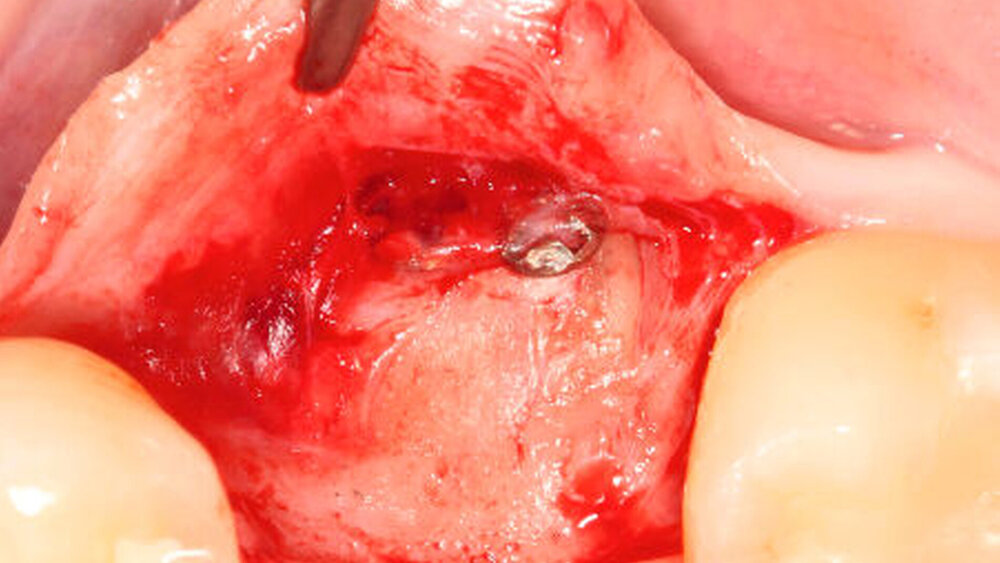

Die hohe Elastizität des Dentins ermöglichte ein hervorragendes klinisches Handling bei der Adaptation und Fixierung (Osteosyntheseschrauben) der Zahnwurzelaugmentate im Defektbereich (Abbildung 2a).

Nach einer plastischen Deckung des Wundgebiets zeigte die Wiedereröffnung nach einer Heilungsphase von zwölf Wochen in allen Gruppen eine vergleichbare homogene Integration der jeweiligen Augmentate im ehemaligen Defektbereich (Abbildung 2b).